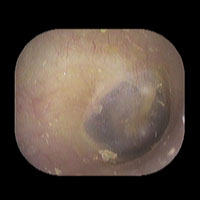

右急性中耳炎(中等症)

鼓膜がやや赤くなっています。鼓膜の奥に膿が透けて見えています。鼓膜の腫れはありません。抗生剤の内服で鼓膜切開を行わずに16日目で治りました。

14日目